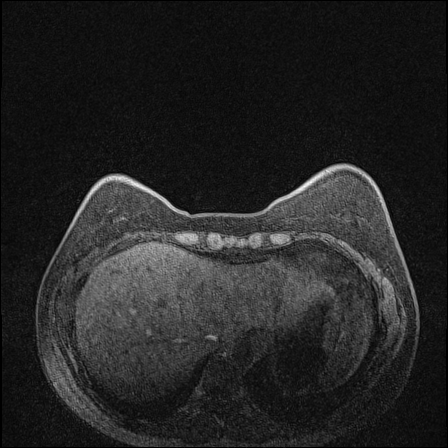

MRI images. The data used in this study are from the DUKE Breast Cancer Dataset [23], a comprehensive single-institutional retrospective collection of 3D MRI scans from over 900 patients with biopsy-confirmed invasive breast cancer at a university hospital. Each study includes a 3D MRI acquired using 1.5T or 3T scanners, from patients in the prone position. On average, each 3D scan consist of 250 2D slices (see Figure 1). For the predictive tasks, the slices are categorized into two groups: those containing breast tumors and those without. Following the approach of [15, 12], we establish a buffer zone between slices containing tumors and those that do not (highlighted in yellow in Figure 1(a)). Images within this buffer zone are excluded from analysis, and the remaining slices are labeled and used for the predictive task.

Magnetic field strength. 3T scanners offer higher magnetic field strength, improving signal-to-noise ratio (SNR) and image resolution for sharper, more detailed images [24]. However, they are more prone to artifacts, heating effects, and signal loss, especially around metal implants [5]. As such, our proposed dataset involving this spurious signal features a non-local spurious signal that influences the entire image rather than a localized region. An example set of images obtained from 1.5T and 3T devices are provided in Figure 3, showing that it is visually not possible to distinguish 1.5T MRIs from the 3T ones.